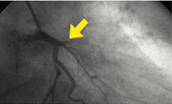

2. 관상동맥 확장술

관상동맥의 좁아진(협착) 정도가 70%이상인 경우 시행되는 관상동맥 확장술로 이상이 있는 관상동맥 내에 유도철선을 삽입하고 풍선도자에 압력을 가해 좁아진 혈관을 확장. 필요시 확장된 혈관 내경을 유지하고 재협착의 발생을 줄이기 위해 스텐트(인체 무해한 금속망)를 삽입하여 고정시키는 시술입니다.